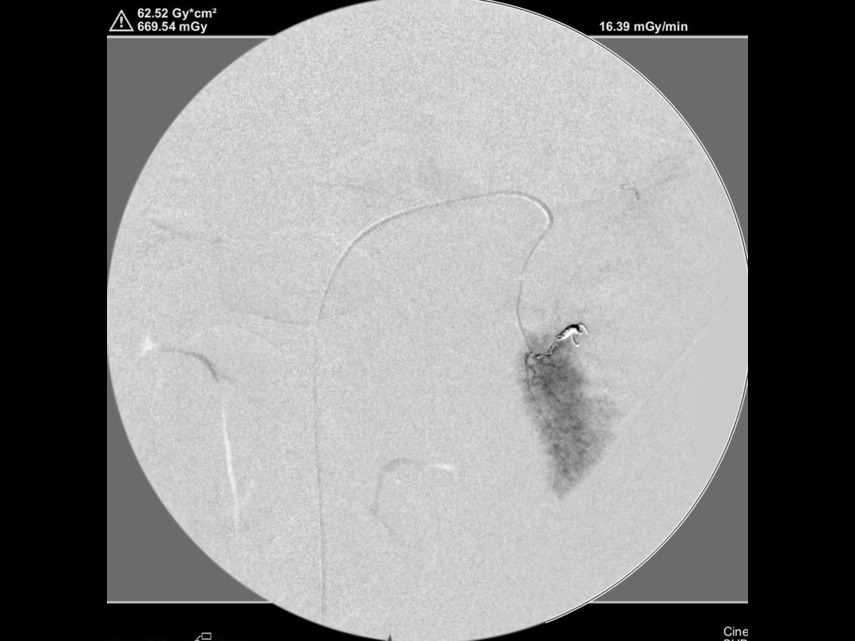

コイル塞栓後の造影検査(脾臓からの出血が止まったことを確認)

肝臓の造影検査を実施し肝臓からの出血がないことを確認